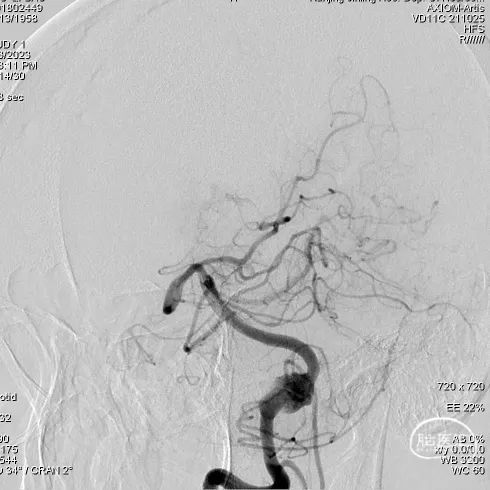

左侧椎动脉造影

右侧椎动脉造影

术后半年复查造影:YonFlow®血流导向密网支架贴壁良好,载流动脉前向血流良好。